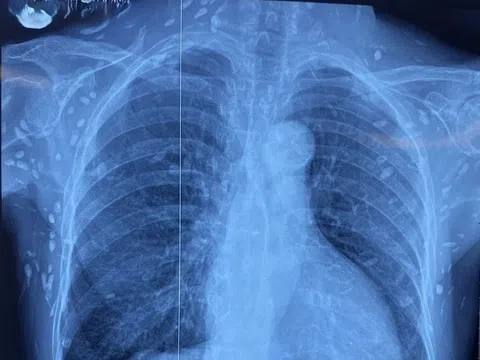

Nghiên cứu cho thấy nhiều người mắc Covid-19 bị mất khứu giác vĩnh viễn. Ảnh: CU Anschutz. |

Mất khứu giác là triệu chứng quen thuộc của người mắc Covid-19, nhưng một nghiên cứu mới do Viện Y tế Quốc gia Mỹ (NIH) dẫn đầu cho thấy tình trạng này có thể vĩnh viễn không hồi phục ở một số người, Independent đưa tin.